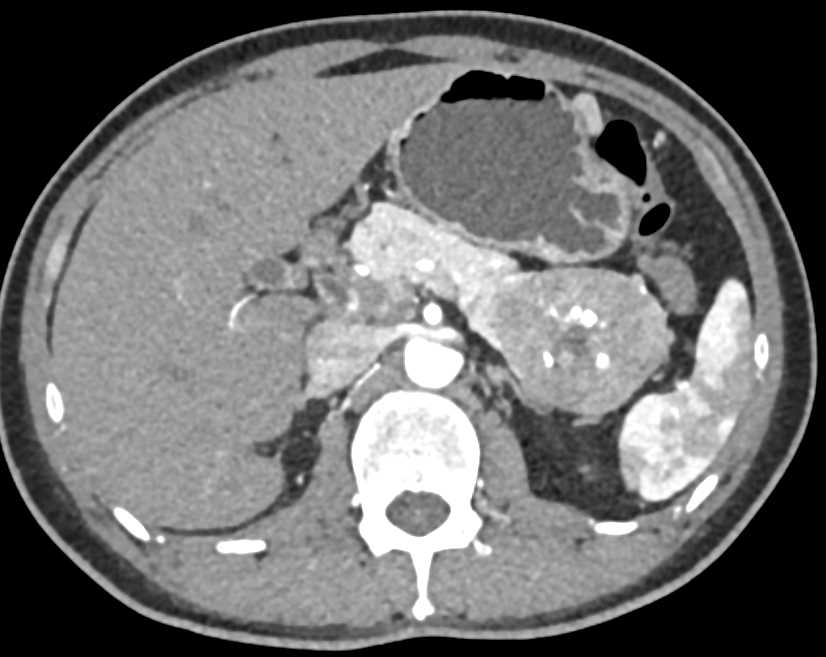

PNET Tail of the Pancreas